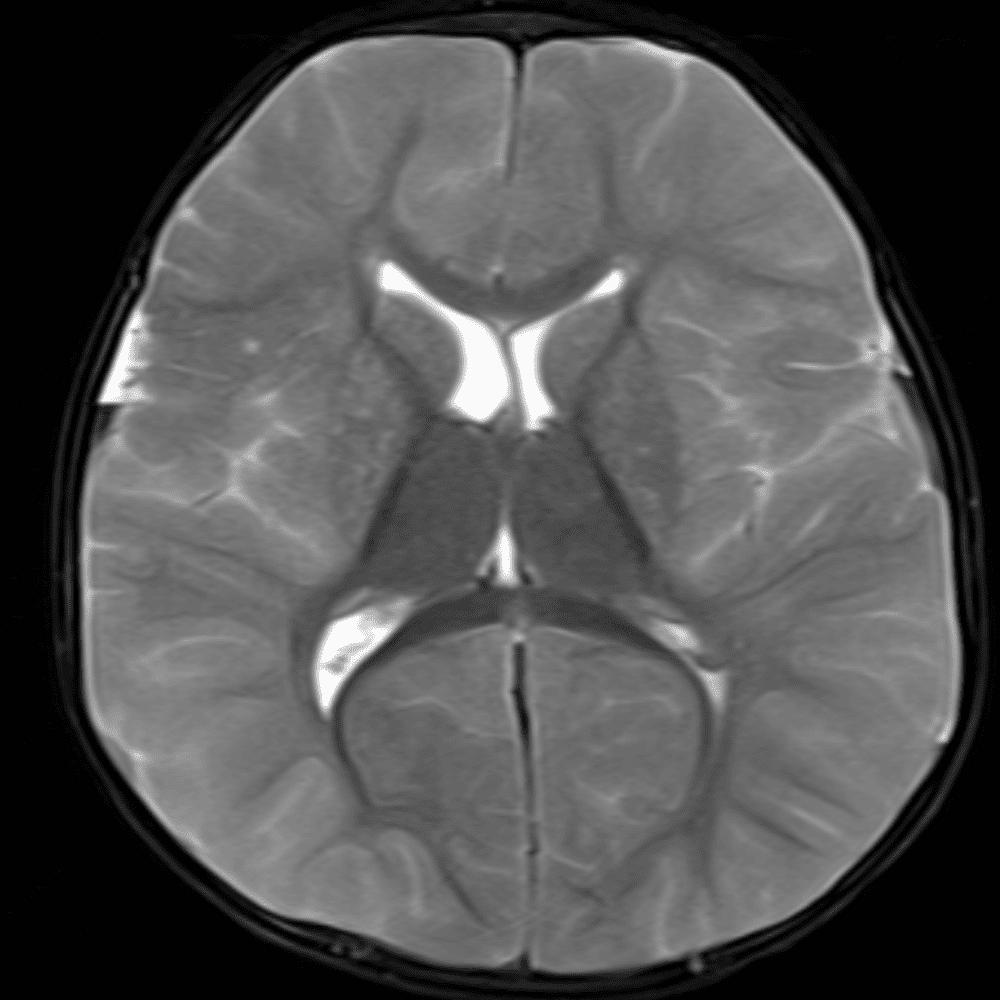

๋‹น์ง ์‹œ ํ”ํžˆ ๋ณผ ์ˆ˜ ์žˆ๋Š” ์‚ฌ๋ก€์˜ ์ „ํ˜•์ ์ธ ์˜ˆ๋ฅผ ํฌํ•จํ•ฉ๋‹ˆ๋‹ค.

39 ์‚ฌ๋ก€

์—ฐ์Šต

๋ฏธ๋ฌ˜ํ•˜๊ฑฐ๋‚˜ ์–ด๋ ค์šด ์‚ฌ๋ก€์™€ ์ผ๋ถ€ ์ •์ƒ ์‚ฌ๋ก€๋ฅผ ํฌํ•จํ•˜์—ฌ ๋‹น์ง์„ ์‹œ๋ฎฌ๋ ˆ์ด์…˜ํ•ฉ๋‹ˆ๋‹ค.

50 ์‚ฌ๋ก€